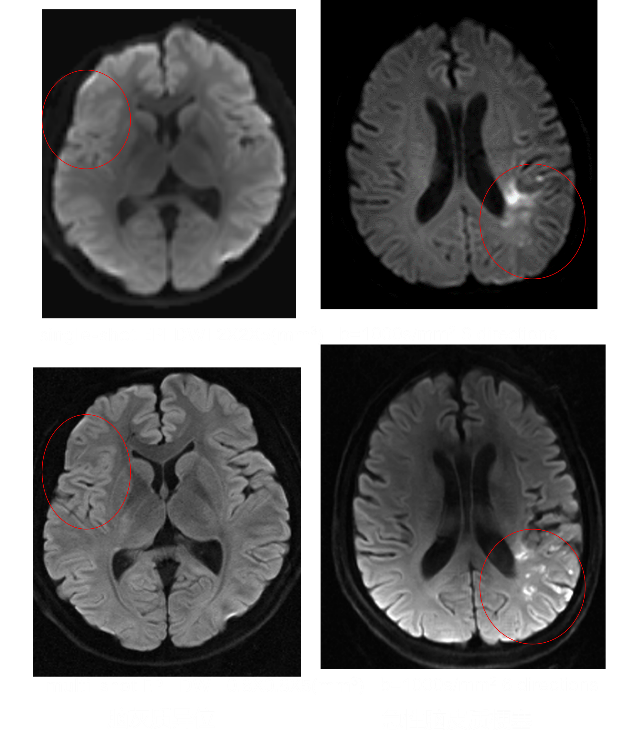

高分辨脑神经系统3D FLAIR成像技术显示局灶性皮质结构发育不良 高分辨脑神经系统mult-shot DWI 与传统single-shot成像技术对比,在脑灰质异位与急性脑皮质梗塞显示中更具优势。 3D SNAP-MRA 显示左大脑中动脉血管中断,3D FLAIR显示左脑萎缩及有功能的左手功能区,fMRI-Bold融合清晰显示功能区,DTI/FT 显示有功能的皮质纤维束。